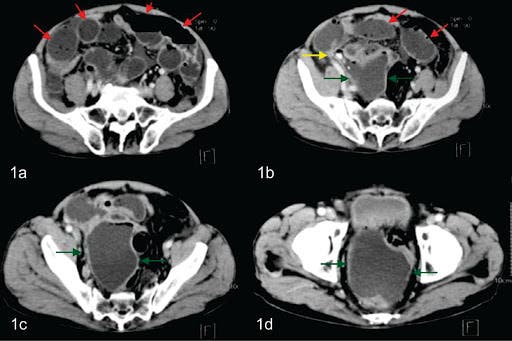

Por su parte la tomografía computada tiene una sensibilidad cercana al 98% y una especificidad que bordea el 100%, permitiendo al radiólogo confirmar este diagnóstico y poder realizar además diversos diagnósticos diferenciales.